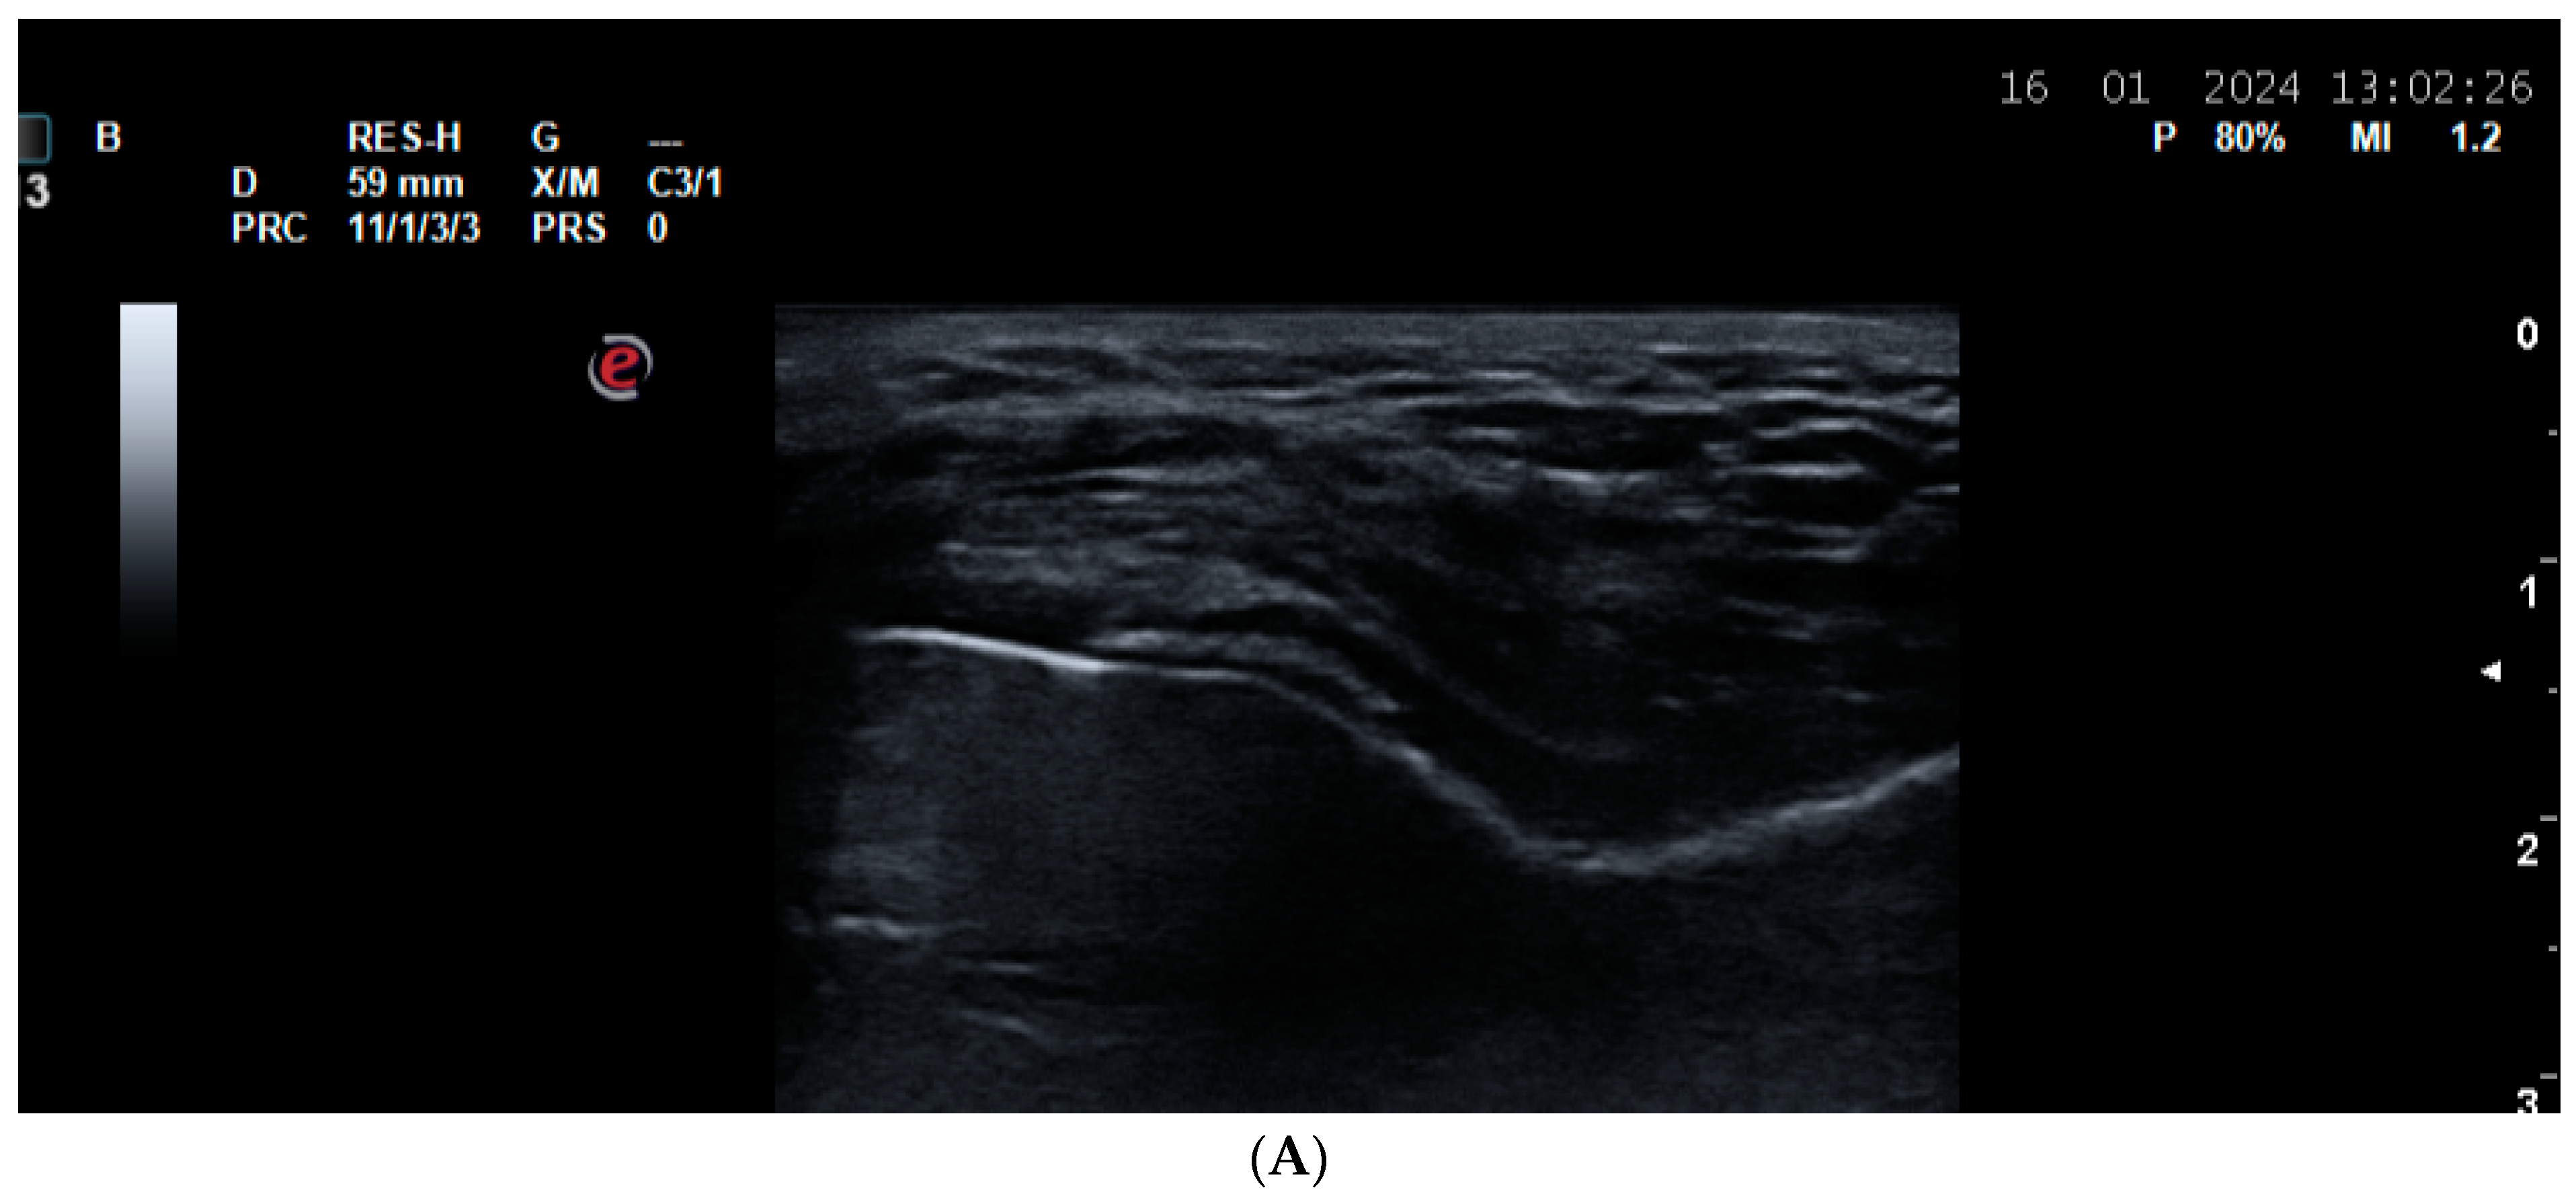

5.1. Polymyalgia Rheumatica (PMR)

- Todorov, P.T.; Batalov, A.Z. Ultrasound description and follow up of painful cervical interspinous bursitis in a Polymyalgia Rheumatica patient—A case report. Med. Ultrason. 2023, 25, 469–471. [Google Scholar] [CrossRef] [PubMed]